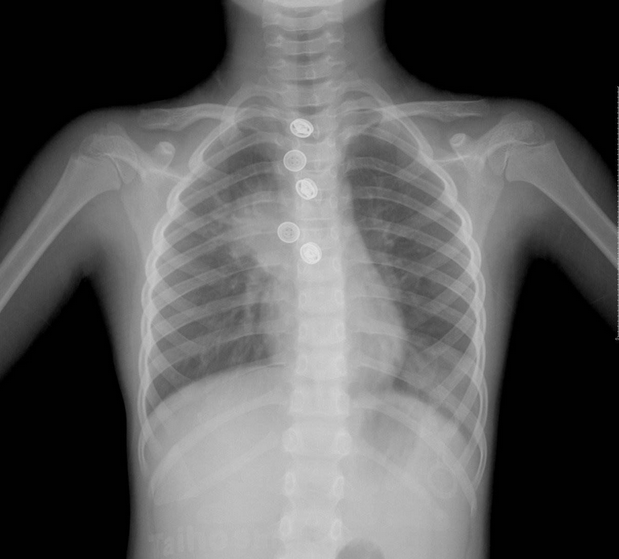

X光手臂透视——1微西弗

谈到X光,许多人还是心有余悸,关于X光透视辐射的新闻时不时就会看到,每次体检选择不做胸透的人也越来越多,事实上一次X光透视的辐射并没有那么夸张,不同部位的透视辐射剂量也不尽相同,例如手臂透视是辐射最小的。

牙齿或手掌X光透视——5微西弗

牙齿和手掌的透视相对高一些,不过仍然是可以忽略不计的。毕竟相比X光,CT的辐射量要大得多。

X光胸部透视——20微西弗

近几年有关胸透的危害屡屡听闻,事实上一次胸透辐射量约20微西弗,并没有那么高,相比CT要低很多。

胸部CT——5800微西弗